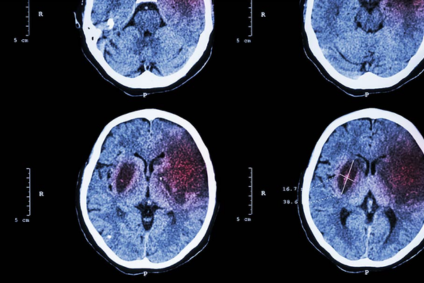

Por otra parte, encontramos el ictus, también conocido como accidente cerebrovascular. El mismo es una de las principales causas de discapacidad y mortalidad a nivel mundial, y ocurre cuando el flujo sanguíneo al cerebro se interrumpe, ya sea por un bloqueo, propio de los ictus isquémicos, o por la ruptura de un vaso sanguíneo, referente a los ictus hemorrágicos. A su vez, los síntomas suelen aparecer de forma súbita e incluyen debilidad en un lado del cuerpo, dificultad para hablar y pérdida de la visión (Kuriakose y Xiao, 2020).

Por el contrario, el ictus aparece de forma abrupta. En cuestión de minutos, una persona puede experimentar parálisis en un lado del cuerpo, dificultades para hablar o pérdida de visión. Dicho inicio súbito refleja su naturaleza vascular, es decir, una obstrucción repentina del flujo sanguíneo en el ictus isquémico o la ruptura de un vaso en el ictus hemorrágico (Schaff y Grommes, 2022).

En contraste, el ictus se confirma con tomografía computarizada o resonancia magnética, que identifican hipoperfusión o hemorragia según el tipo. A su vez, el ictus isquémico requiere trombólisis o trombectomía, mientras que el hemorrágico demanda cirugía para controlar la hemorragia y reducir la presión intracraneal (Kuriakose y Xiao, 2020).